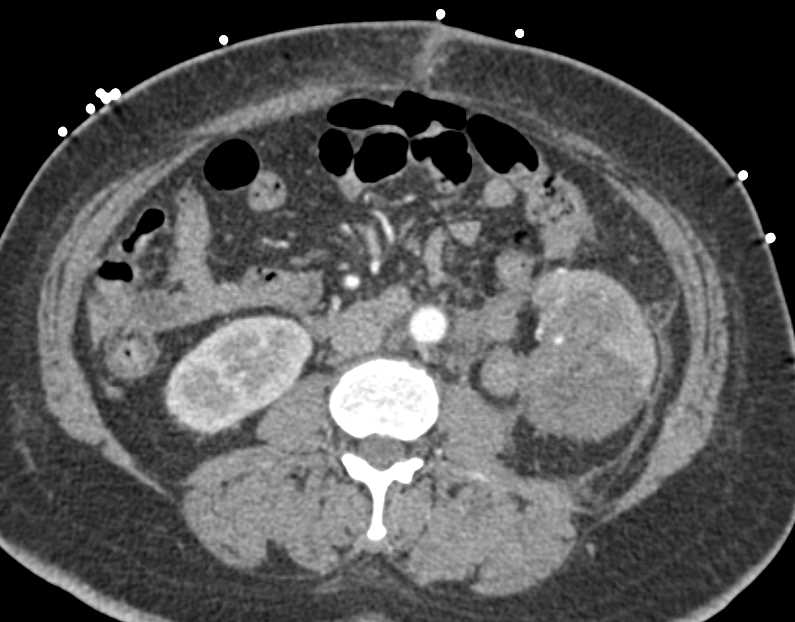

Acute Pyelonephritis Right Kidney